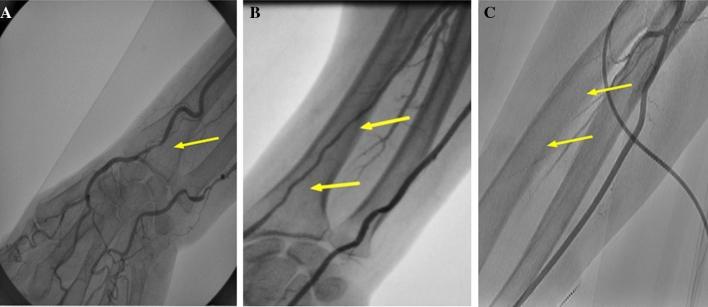

The transradial approach for percutaneous coronary intervention (TRA-PCI) has been increasingly gaining popularity in clinical practice. However, its association with risk for long-term radial artery injury has not been yet thoroughly defined. We retrospectively examined the patients undergoing radial artery angiography (RAG) after TRA-PCI to determine the incidence and risk factors of radial artery injury. The study included 558 patients undergoing follow-up radial artery angiography at 12 month after TRA-PCI. Radial artery injury occurred in 140 patients (25%) with 3 distinct morphological patterns: focal radial artery stenosis (RAS) P.7,7: in 7 patients (1%), diffuse radial artery stenosis (RAS) in 78 patients (14%), and radial artery occlusion (RAO) in 55 patients (10%). Patients with RAS/RAO were more likely to be female, had smaller height and body weight, smaller body mass index and smaller body surface area (BSA) as compared with those without RAS/RAO. Multivariable logistic regression analysis identified BSA (odds ratio, 1.34 per 0.1 m increase; 95% confidence interval, 1.07-1.71; p = 0.01) and a history of TRA-PCI (odds ratio, 2.35; 95% confidence interval, 1.16-5.08; p = 0.017) as independent predisposing factors of radial artery injury. In a sub-analysis of 323 patients undergoing both pre-PCI RAG and follow-up RAG, pre-PCI radial diameter as well as BSA and a history of TRA-PCI were independently associated with radial artery injury. Long-term injury after TRA-PCI is considerably common and care should be paid for RAS/RAO, especially for those patients with lower BSA, history of TRA-PCI and small radial artery diameter.

经桡动脉入路行经皮冠状动脉介入治疗(TRA-PCI)在临床实践中越来越受欢迎。然而,其与长期桡动脉损伤风险的关系尚未得到充分定义。我们回顾性检查了接受 TRA-PCI 后行桡动脉造影(RAG)的患者,以确定桡动脉损伤的发生率和危险因素。该研究纳入了 558 例接受 TRA-PCI 后 12 个月随访桡动脉造影的患者。桡动脉损伤发生在 140 例患者(25%)中,有 3 种不同的形态学类型:桡动脉局灶性狭窄(RAS),7 例(1%);桡动脉弥漫性狭窄(RAS),78 例(14%);桡动脉闭塞(RAO),55 例(10%)。与无 RAS/RAO 的患者相比,有 RAS/RAO 的患者更可能为女性,身高、体重、体重指数和体表面积(BSA)较小。多变量 logistic 回归分析确定 BSA(优势比,每增加 0.1m 增加 1.34;95%置信区间,1.07-1.71;p=0.01)和 TRA-PCI 史(优势比,2.35;95%置信区间,1.16-5.08;p=0.017)是桡动脉损伤的独立危险因素。在 323 例同时接受 PCI 前 RAG 和随访 RAG 的患者的亚分析中,PCI 前桡动脉直径以及 BSA 和 TRA-PCI 史与桡动脉损伤独立相关。TRA-PCI 后长期损伤相当常见,应注意桡动脉狭窄/闭塞,特别是 BSA 较低、有 TRA-PCI 史和桡动脉直径较小的患者。